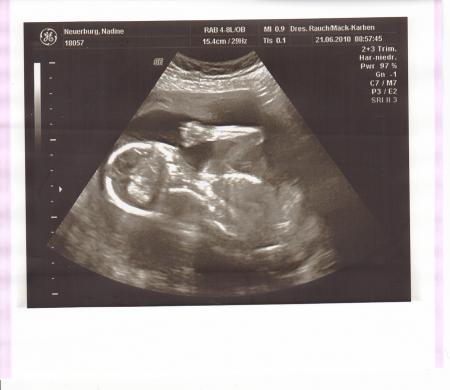

..und hier ist er mein Mini Me:-) Alles zeitgerecht gewickelt und meine Werte sind auch alle bestens:-) Nächste Vorsorge hab ich dann zur Abwechslung mal bei meiner Hebi am 19.7.,weil sie auch meine Geburt begleiten wird

Bild zu Heute wieder VU/ 2tes großes Screening 19 SSW - Forum für November - Mamis

Hier die Werte:-) BPD 45 FOD/KU 51 ATD 43 APD/AU 129 FL/HL 28